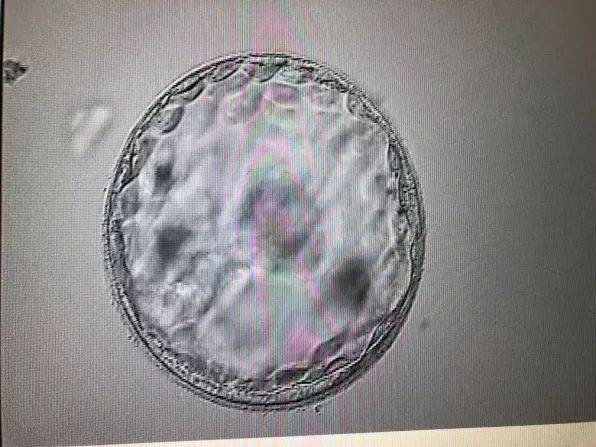

卵泡破裂是指成熟卵泡在排卵期破裂,卵细胞从中释放出来,进入输卵管,准备与精子结合。这一过程受到多种因素的影响,如激素水平、卵巢功能等。